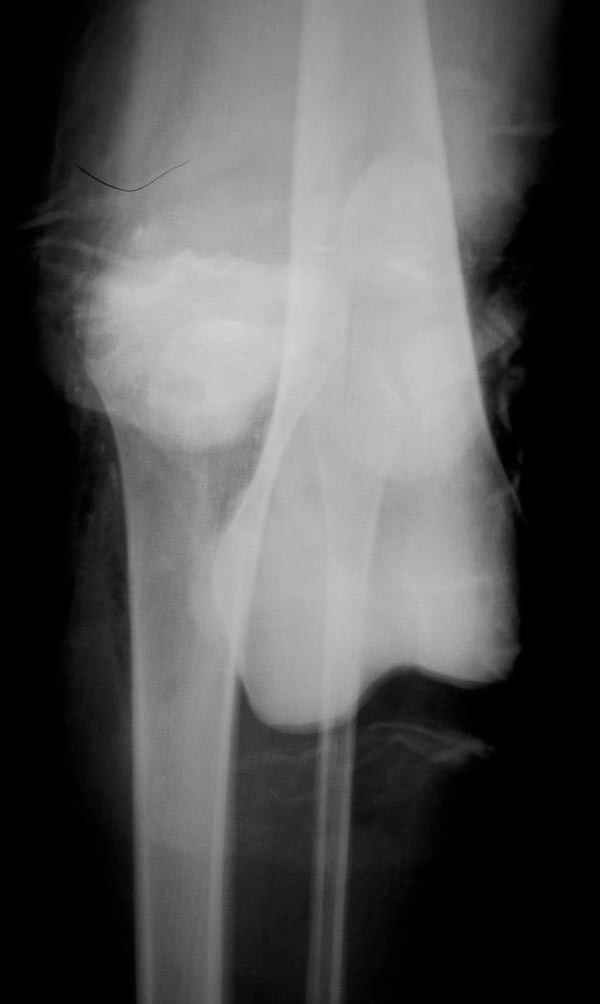

В приемное отделение поступает больная 22 лет, во время аварии ремень безопасности не был пристегнут, в крови большое количество кокаина.В приемном срочная интубация и седация, сделаны снимки.Диагностирован: открытый вывих левого коленного сустава.

Заключительный диагноз: Открытый вывих коленного сустава, перелом надколенника, разрыв собственной связки надколенника

Сегодня досылаю остальные снимки, которые не прошли вчера. Как вчера писал, после фиксации перелома надколенника с дефектом кости и собственной связки, наложили ваккуум и наружный фиксатор. (снимки 4-9)

На слайдах (не четко обозначены бедро и голень): на бедре по наружно-передней поверхности, между вастус латералис и прямой головками, а на голени по передне-медиальной поверхности, желателен подбор длины резьбовой части стержня по ширине поперечника кости. На снимке: дистальное кольцо, метод проведения стержня через канюлю-проводник.